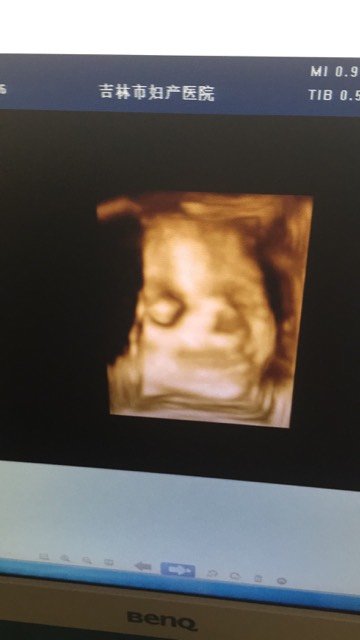

看看我的大宝贝,能看出男孩女孩吗,不过都说像我,呵呵,宝妈们,我25周,羊水3.98CM,少不少

看看我的大宝贝,能看出男孩女孩吗,不过都说像我,呵呵,宝妈们,我25周,羊水3.98CM,少不少,还有,开春了,我感冒了,鼻子不通气,打喷嚏,体温37度,有危险吗,好怕怕